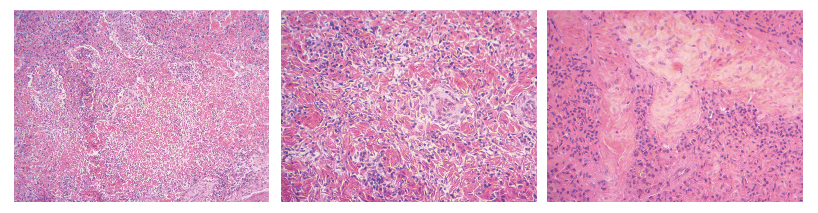

三、結果提供 細胞核被染成深藍黑色;細胞漿被染成粉紅色;軟骨及鈣鹽被染成藍色;膠原纖維染成淡粉紅色,嗜酸性細胞及嗜酸性顆粒呈鮮紅色;彈力纖維呈淡粉紅色;某些蛋白性物呈粉紅色等。

結果展示